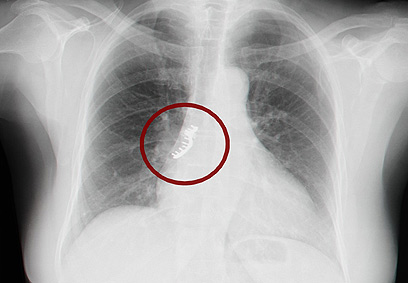

"פתאום התחלתי להשתעל באופן לא ברור", משחזרת דינה, "לא הבנתי מה קורה". כשפנתה דינה לרופא המשפחה, זוהה בצילום הרנטגן גשר של שיני ברזל. דינה הופנתה מיד לחדר המיון של בית החולים כרמל.

צילום החזה שגילה את הגשר המחודד (צילום: אלי דדון)